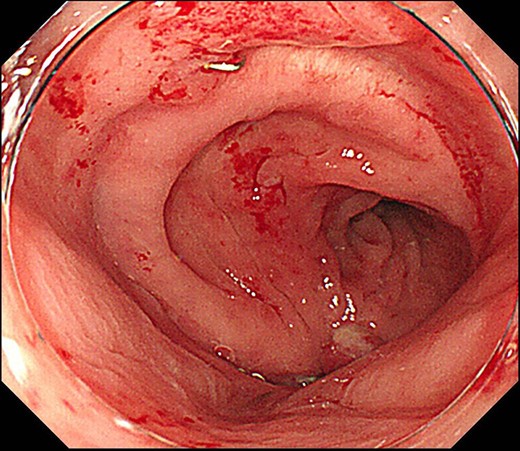

Case 1 was a 71-year-old man with a BMI of 29.7 kg/m2. Laparoscopic low anterior resection (LAR) and ileostomy was performed for rectal cancer in 2017 years. Postoperative fever and lower abdominal pain were noted, and colonoscopy was performed, and anastomotic leakage was noted with a correction of about 1/2 around the 6 o’clock direction of the anastomotic region, and fistula and formation of a large abscess cavity. After identification (Fig. 1), a tube was inserted for drainage and conservative treatment was performed. The patient was discharged on POD 46. Four months after the operation, marked improvement in the abscess cavity was noted but still remained (Fig. 2a and b). Anastomotic leakage was almost improved by colonoscopy at 17 months after surgery, but at the preference of the patient we performed colostomy 22 months after surgery (Fig. 3). It took a long time to improve intestinal movement of the colon because the large intestinal tract had not been used for a long time, and conservative treatment was performed using a nasogastric tube for paralytic ileus. Diet was initiated 7 days after surgery, and the patient was discharged from the hospital 14 days after surgery. The Wexner score [2] was 19 points one month after closure, 17 points 3 months after the operation and 16 points after 6 months after the operation, and severe anal dysfunction was observed, but gradually improved.

(a) Colonoscopy shows a fistula (arrow). (b) Enema examination shows a cavity (arrow) leading from the fistula.